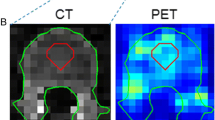

Overall analysis time per scan incorporating the manual segmentation method was approximately 4 h compared to ≤ 30 min when AI-based segmentation was used. Example patient images, including whole organ segmentations, are shown in Fig. 1. A comparison of organ volumes obtained using the two different segmentations methods is illustrated with scatter plots in Fig. 2. The segmented volumes using manual and AI-based segmentation in the kidneys (P = 0.005), in the liver (P < 0.001), and in the spleen (P < 0.001) were significantly different. Median Jaccard similarity coefficients between manual organ VOI segmentations and AI-based segmentations varied from 0.05 (range 0.00–0.14) for the pancreas to 0.78 (range 0.74–0.82) for the lung. A complete overview of Jaccard similarity coefficients is provided in Table 1.

The manual segmentations performed in this study showed some inaccuracies, for example, inclusion of a small part of the inferior vena cava in the liver segmentation, and exclusion of the border of the kidney, see Fig. 1. Also, the AI-based segmentations showed imperfections, for instance in the kidneys, spleen, and pancreas as can be seen from Jaccard values (Table 1), in Fig. 4, and Supplemental Fig. 1. This pilot study showed however that effective dose estimation is accurate (within 2%) regardless of these variations in manual or AI-based organ segmentation. Since whole-body dosimetry involves the summation of weighted dose values from multiple organs and structures, effective dose calculation is less susceptible to variabilities that arise by the type of segmentation method.

The low-dose CT dataset used in the current study showed streak artifacts in some cases. Example images, including whole organ segmentations, are shown in Fig. 4. These were the cases in which the pancreas was not accurately segmented by the AI-based tool, but also the kidneys, liver, and the spleen showed differences in segmented volume. These volumetric differences did not lead to inaccurate effective dose estimates in this small dataset. However, for smaller or other antibody moieties, accuracy and precision of organ segmentation may be more critical to obtain reliable dose estimates. The developers of the tool confirmed that in the training set of the CNNs, no image artifacts, such as streak artifacts observed in our data, were included. To overcome these issues in future work, a convolutional neural network could be trained to handle these data, including streak artifacts. At this time, we recommend that AI-based segmentations should be supervised by an observer and corrected when needed. Nonetheless, with respect to manual delineation, a considerable amount of time can be saved by supervised AI-based whole organ segmentation.